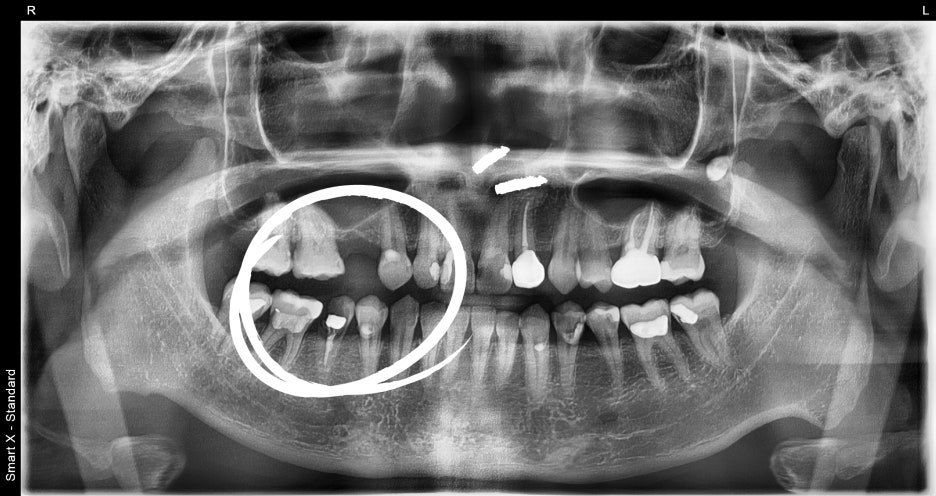

Photo at the first visit

Panoramic imaging showed that the lower right molar had fractured

and could not be preserved.

It was diagnosed as a case in which immediate implant placement after extraction was possible.

The upper right premolar had been missing for a long time,

but because the degree of bone resorption in the jawbone was not severe,

implant treatment was possible without additional bone grafting.